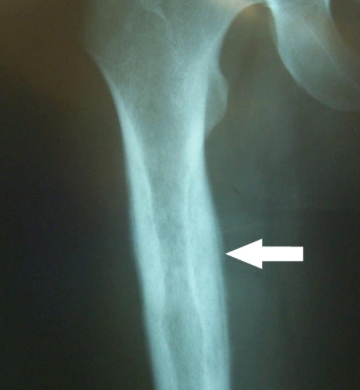

Osteosarcoma

Demographics: Occurs most commonly in the second decade of life, and a bit more commonly in boys than in girls. It occurs in all ethnic groups (in contrast, Ewing sarcoma, another bone malignancy, rarely occurs in blacks).

Symptoms: The lesion is found in the metaphyses of long bones, and usually presents with local pain and swelling.

Labs: Radiograph shows the expected “sunburst” pattern of bone formation.

Risks: Predisposing factors include a history of retinoblastoma, Li-Fraumeni syndrome, Paget disease, or radiotherapy. Any bone or joint “injury” not responding with conservative therapy within a short period of time should be evaluated.,

Over the previous 2 to 3 weeks, a very active 13-year-old white boy is noted by his family to have developed deep pains in his leg that awaken him from sleep. The family brings him to your office with a complaint of a swelling over his distal leg, which he attributes to his being kicked while playing soccer about 1 week ago. He has had no fever, headaches, weakness, bruising, or other symptoms. A radiograph of the leg is shown below. Which of the following is the most likely explanation for his pain?